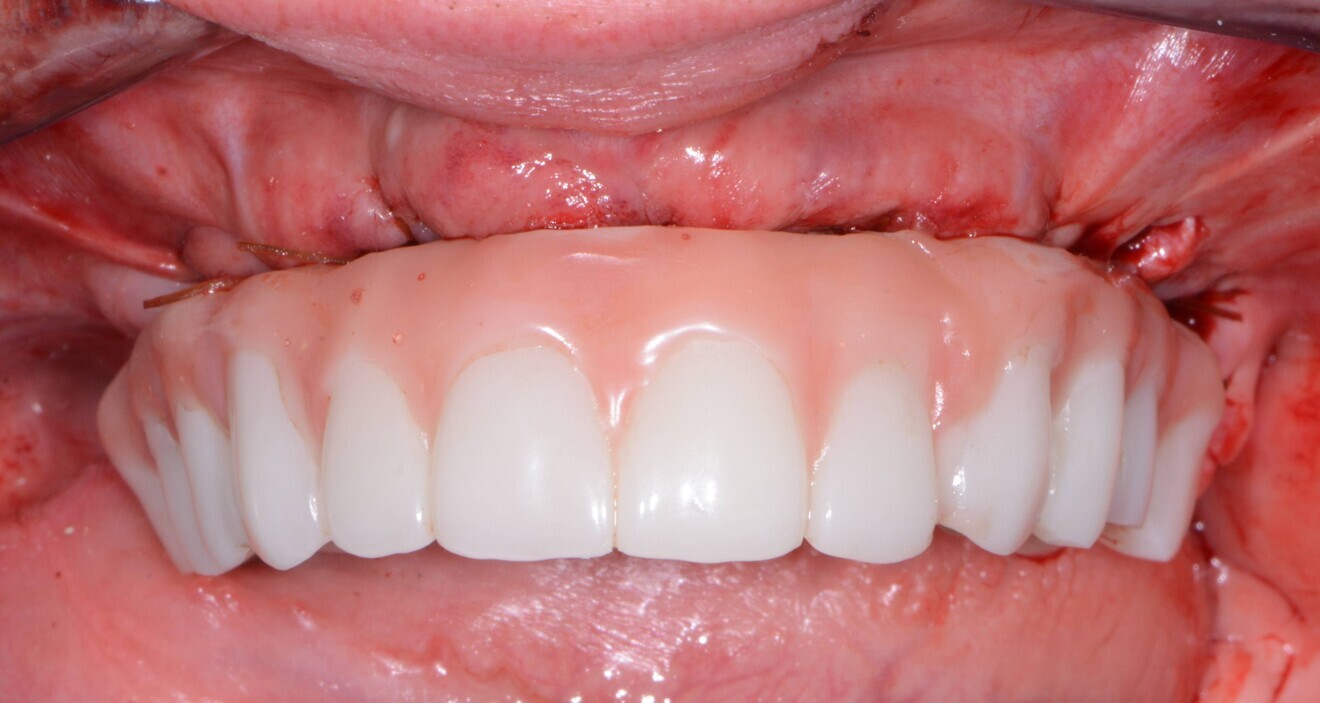

The maxillary provisional restoration was tried in to verify a passive fit over the temporary abutments. Once fit had been confirmed, trimmed dental dam pieces (COLTENE) were placed to avoid the restoration (Fig. 11) locking on during the relining procedure with REBASE III FAST hard relining material (Tokuyama Dental). After the material had polymerised, the immediate provisional restoration was removed and excess material was removed with the Torque Plus laboratory handpiece (Aseptico) and an acrylic bur (Komet). Once trimmed and polished, the provisional restoration was seated and tightened with a torque wrench to 15 N cm (Fig. 12). The access openings were filled in three-quarters of the way with PTFE tape, followed by Cavit filling material (3M ESPE).

Fig. 11: Maxillary provisional restoration positioned on the guide.

Fig. 12: Maxillary provisional restoration in situ.